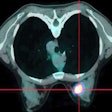

PET/CT's role develops in breast cancer follow-up